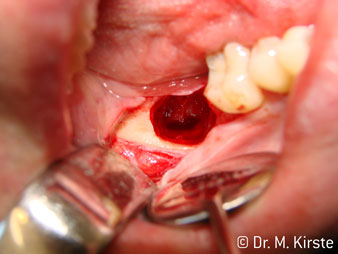

45° açılı angldruva geniş avantaj yelpazesi sebebiyle özellikle seçildi. Bu enstrümanın geliştirilme nedeni olan cerrah meslektaşlarım angldruvaların kısıtlı alanlardaki çalışma yeteneğini yakında takdir edeceklerdir. Özellikle gömük diş çekimlerinde (res. 2) yumuşak dokunun yanak bölgesine doğru yarılmasına gerek kalmaz(res. 3). Angldruvanın kafa dizaynı sayesinde retromolar bölgede hızlı ve güvenli çalışma sağlar.

Angldruva kafası içindeki profesyonel tasarımlı dişliler frezin sessiz çalışmasını garanti eder; kök separasyonu yapılırken atravmatik operasyona olanak verir. (res. 4-9).

45° açılı angldruva çok rahat kavranıyor. Angldruva çalışırken işaret parmağınızın açısını takit ettiğini görebilirsiniz, planladığınız işlemi kusursuz bir şekilde tamamlarsınız. (res. 1)”